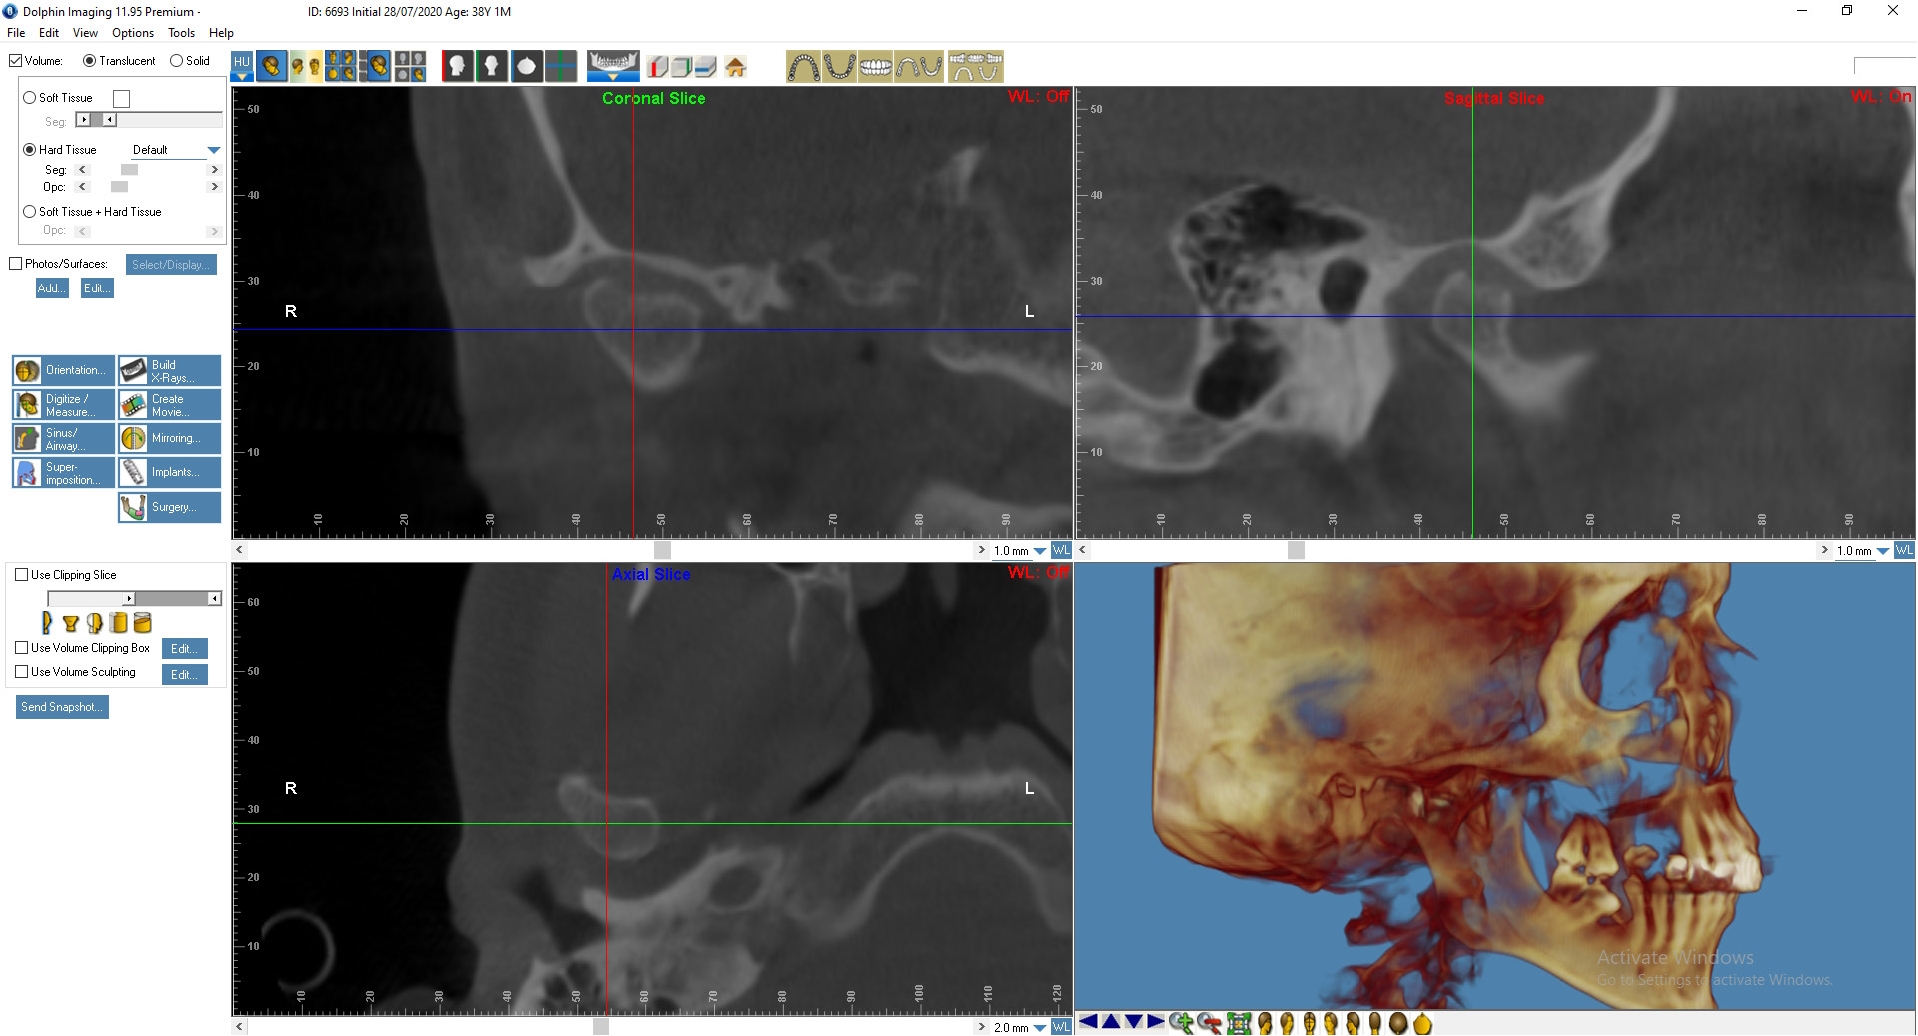

По данным МРТ ВНЧС спустя 2 года после начала лечения отмечается устранение вентро-латеральной дислокации суставного диска в положении привычной окклюзии. Также устранен синовит, увеличился объем движения в суставе (рис. 5). Как видно из рис. 4 и 5, по данным КТ ВНЧС спустя 2 года после начала лечения отмечается ремоделирование головки нижней челюсти. Клинически увеличилось открывание рта до 38 мм.

Рис. 4. Пациент Д., 38 лет. КТ ВНЧС до начала лечения

Рис. 5. Пациент Д., 40 лет. КТ ВНЧС спустя 2 года после начала лечения